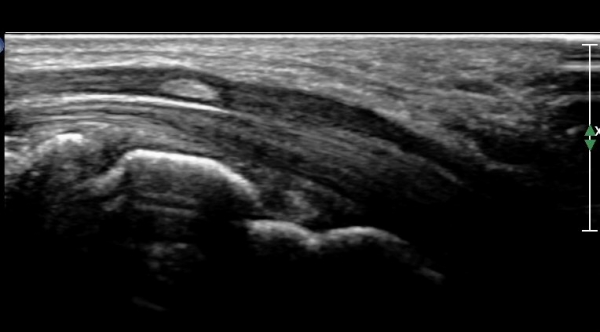

ÆÄ¿öµµÇ÷°¸Ó»ç»ó Ç÷·ùÁõ°¡´Â °üÂûµÇÁö ¾Ê´Â´Ù(»çÁø 4).